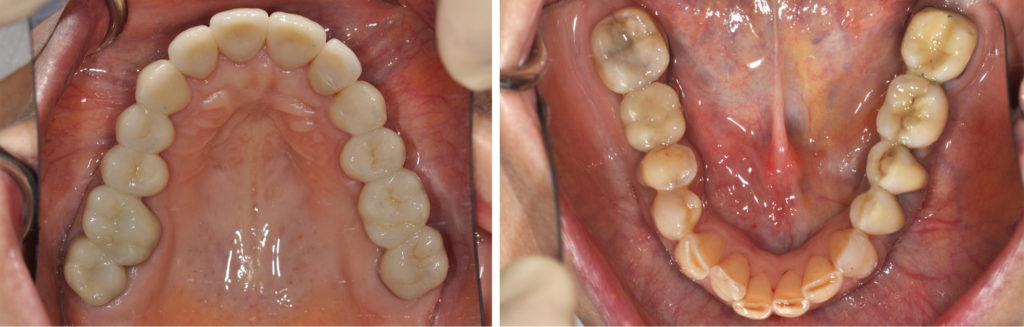

Fig. 2a à 2f : vues intra-buccales de la situation initiale

Analyse dentaire :

• les dents 14, 25, 26, 36 et 46 ont toutes été extraites pour des raisons de délabrements des tissus dentaires (et non pas pour des raisons parodontales),

• les dents 17 et 16 sont dévitalisées et porteuses de coiffes céramo-métalliques dont les limites vestibulaires sont exposées. La dent 36 est remplacée par un bridge céramo-métallique de 4 éléments en appui sur les dents 34, 35 et 37 (dévitalisées),

• les dents 11, 22, 27, 44, 45 et 47 présentent des obturations coronaires en composite qui présentent des signes d’infiltration,

• toutes les les autres dents présentent des signes d’érosion avancée avec des plages d’exposition dentinaires, larges par endroit, vestibulaires, linguales et/ou occlusales.